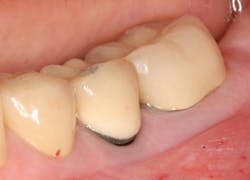

A patient had four quadrants of scaling and root planing in the office of her general dentist. Subsequently, three maxillary anterior implants were placed. The patient was scheduled every six months for periodontal maintenance visits. Radiographs taken prior to the scaling and root planing (figure 4) revealed moderate periodontitis with slight vertical bone loss involving the mandibular left first molar. A deep vertical osseous defect on the distal of the second molar was present.